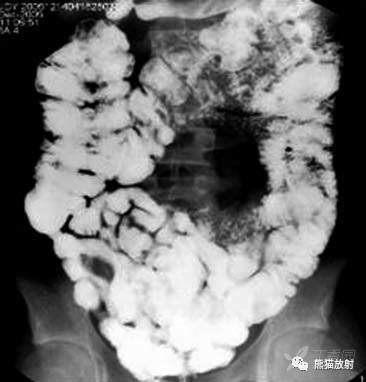

回盲部肠腔持续性狭窄

盲肠短缩伴末端回肠悬吊

回盲部环形缩窄

CT显示回肠末端和盲肠壁增厚伴肠石,周围间隙混浊

盲肠壁增厚伴周围炎性改变